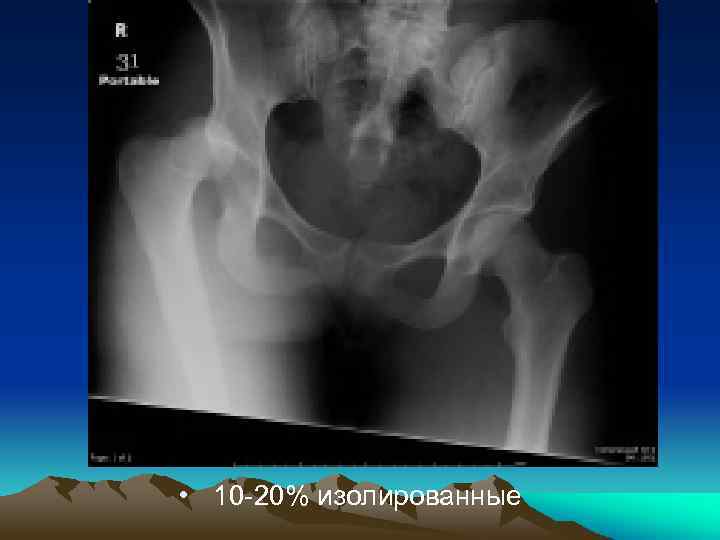

• 10 -20% изолированные

Thomas and Epstein классификация Тип I Изолированный вывих. Тип II Вывих с переломом заднего края впадины (значительный фрагмент). Type III Вывих с компрессией заднего края. Type IV Вывих с переломом дна впадины. Type V Вывих с переломом головки бедра.